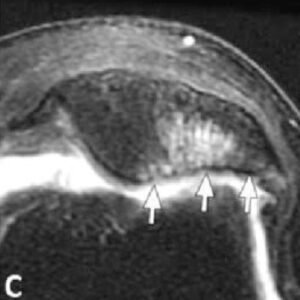

Chondromalacia patellae grades II–IV in various patients.

(C) Axial PD MR image of chondromalacia patellae grade IV in a 63-year-old female. There is extensive full-thickness chondral loss along the medial patellar facet. There is also associated marrow oedema and cystic change within the adjacent bone of the patella (arrows).